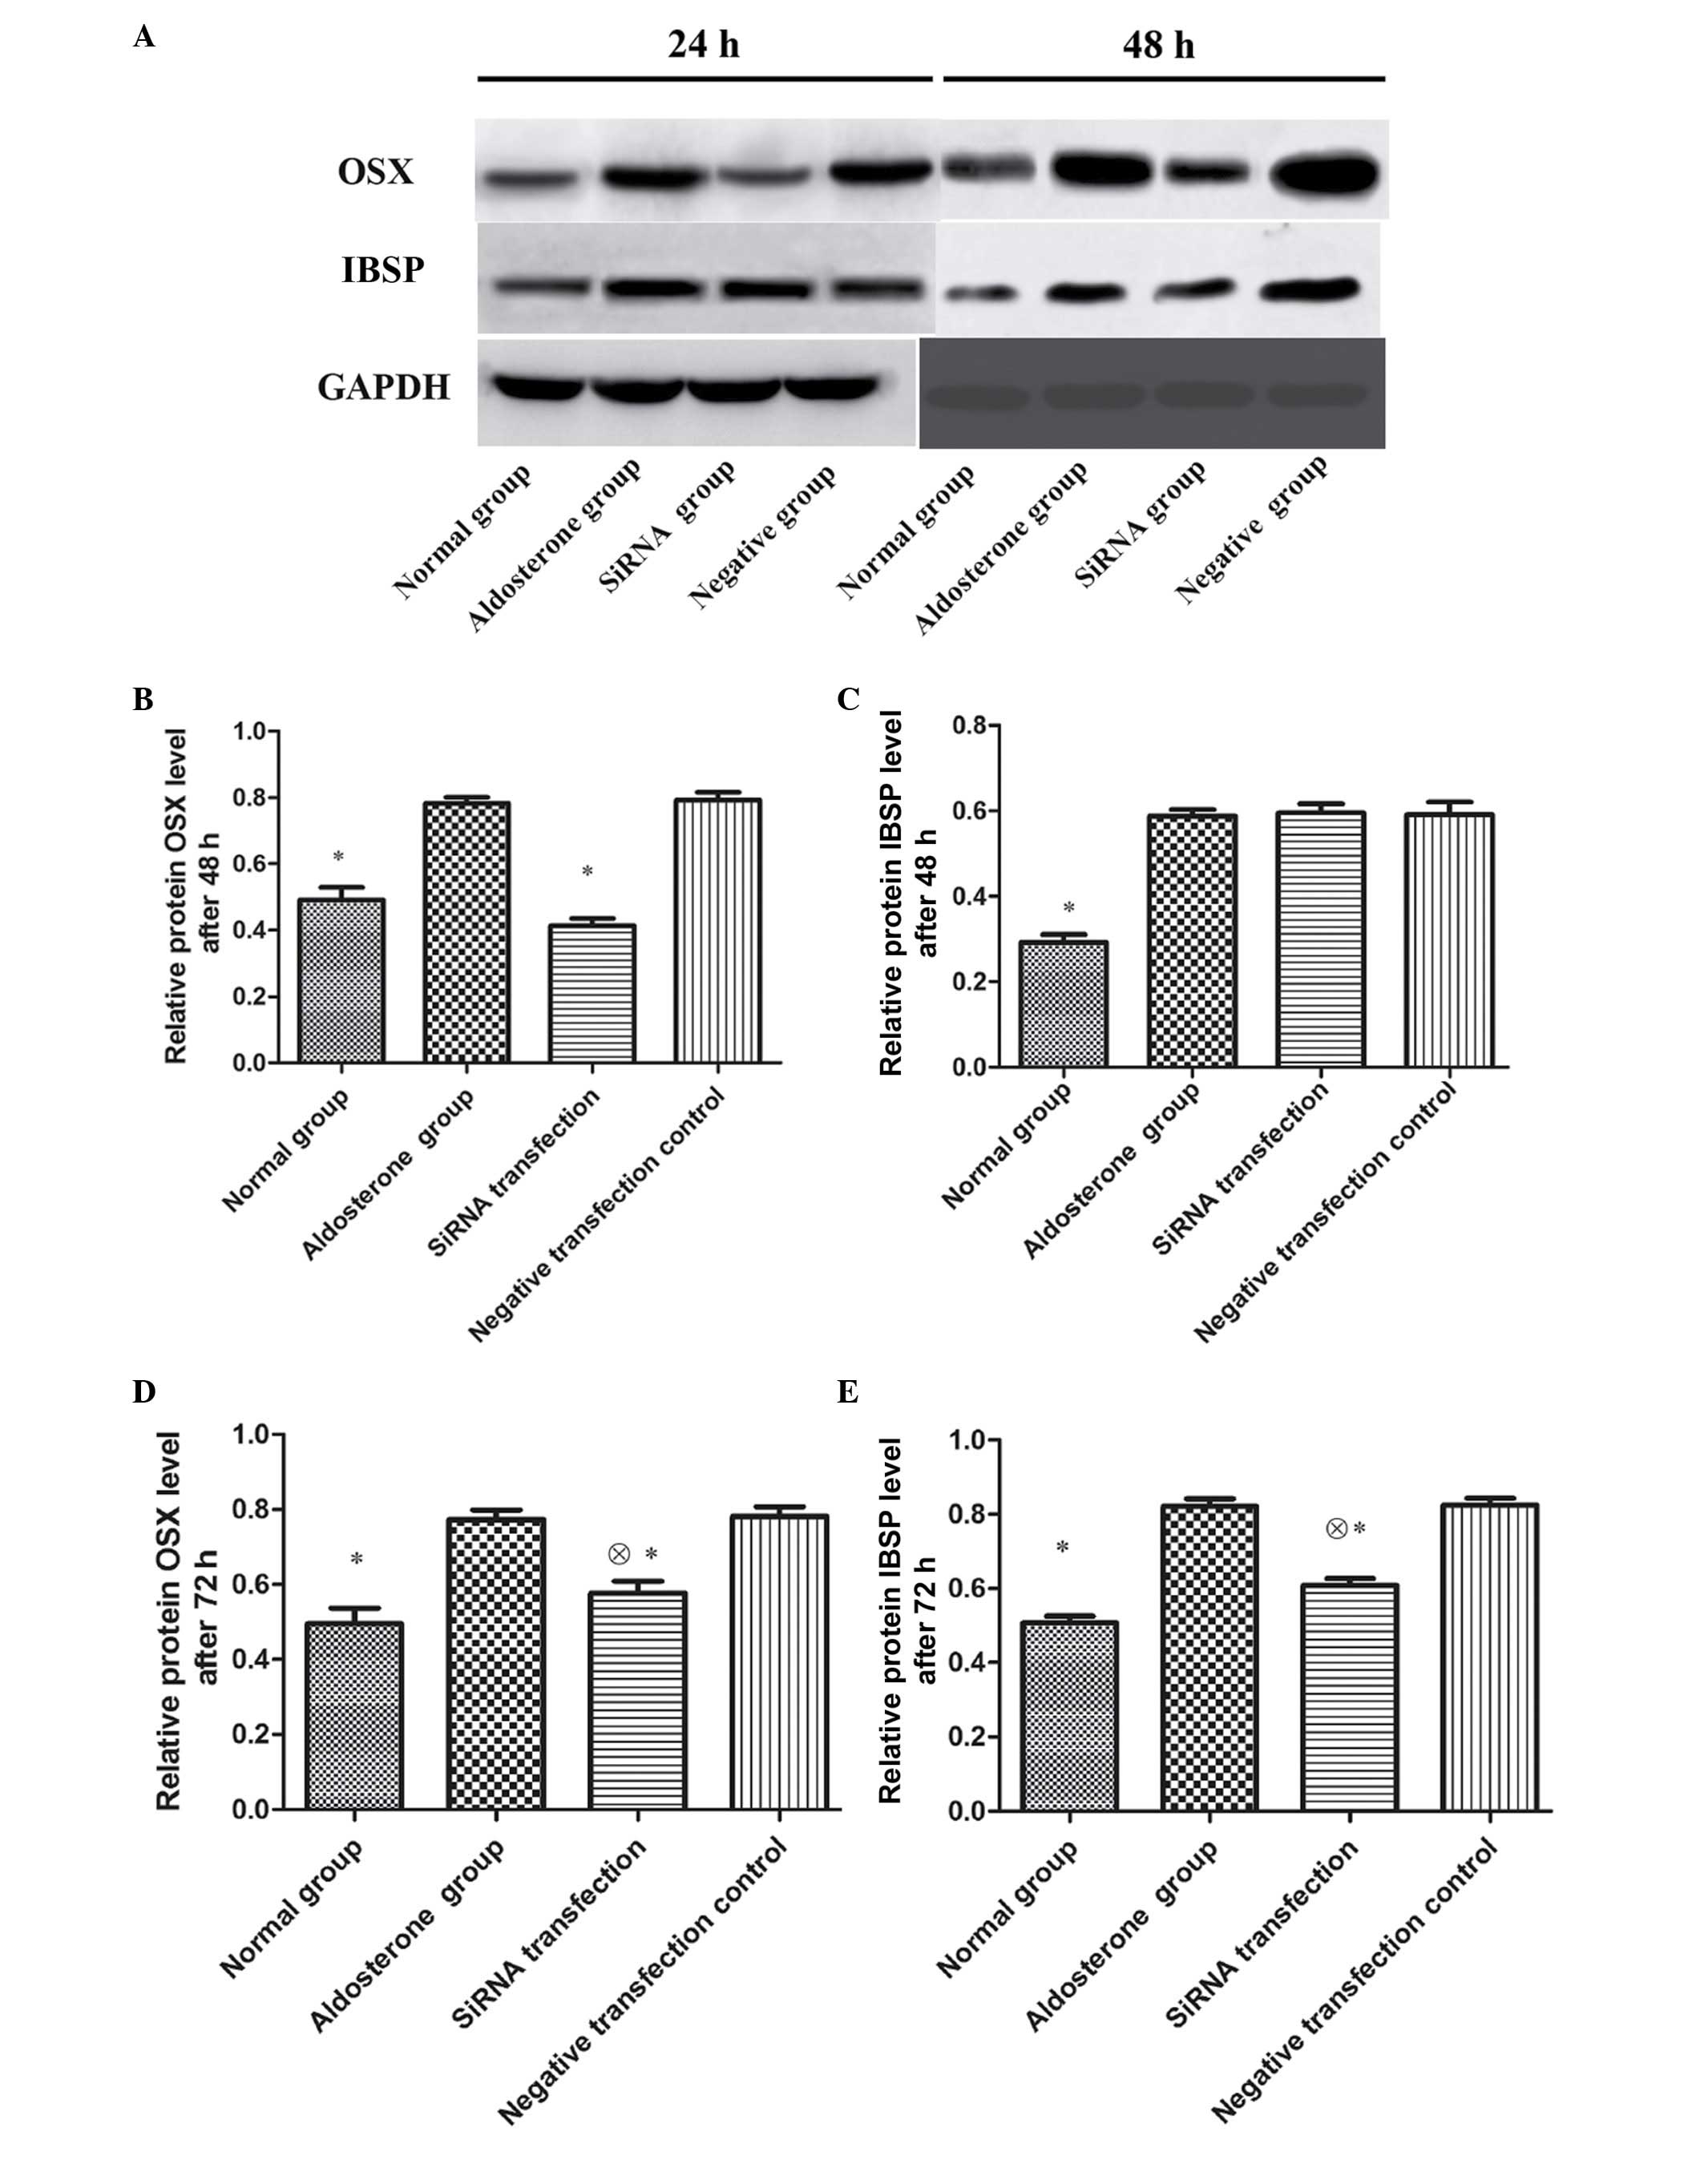

Subsequent to 48-h transfection, OSX and IBSP

protein expression in VSMCs of ALD group was significantly

upregulated as compared with that of the normal group (P<0.01);

the OSX protein expression in the siRNA transfection group was

significantly reduced compared with that of the ALD and negative

transfection control groups (P<0.01). No significant differences

were observed in IBSP protein expression between the three groups

(P>0.05). Subsequent to 72-h transfection, the OSX protein

expression in the siRNA transfection group reamained significantly

lower than that of the ADL and negative transfection control groups

(P<0.01), however was higher than that of the normal group

(P<0.01). The IBSP protein expression in the siRNA transfection

group was significantly lower than that of the ADL and negative

transfection control groups (P<0.01), however was higher than

that of the normal group (P<0.01) (Fig. 4).